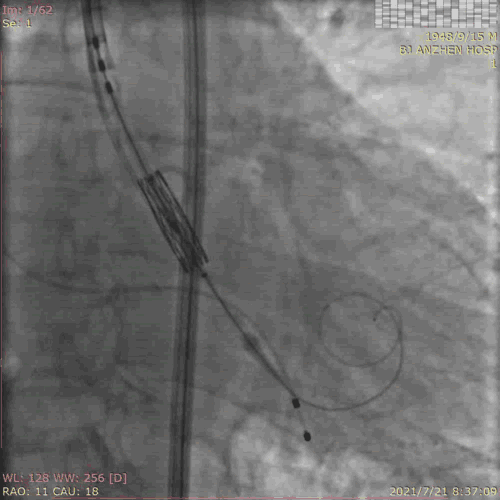

TAVR过程:患者局麻后,植入临时起搏器,穿右股动脉送入23mm球囊预扩张病变,左、右冠状动脉未受明显影响,决定直接植入爱德华SAPIEN 3 26mm 球扩式瓣膜,选择标准位进行释放。

释放后主动脉窦造影提示瓣膜膨胀良好,主动脉瓣周少量反流。术后即刻TTE提示跨瓣最高流速109cm/s,平均跨瓣压差3mmHg。主动脉瓣瓣口面积2.72cm²。